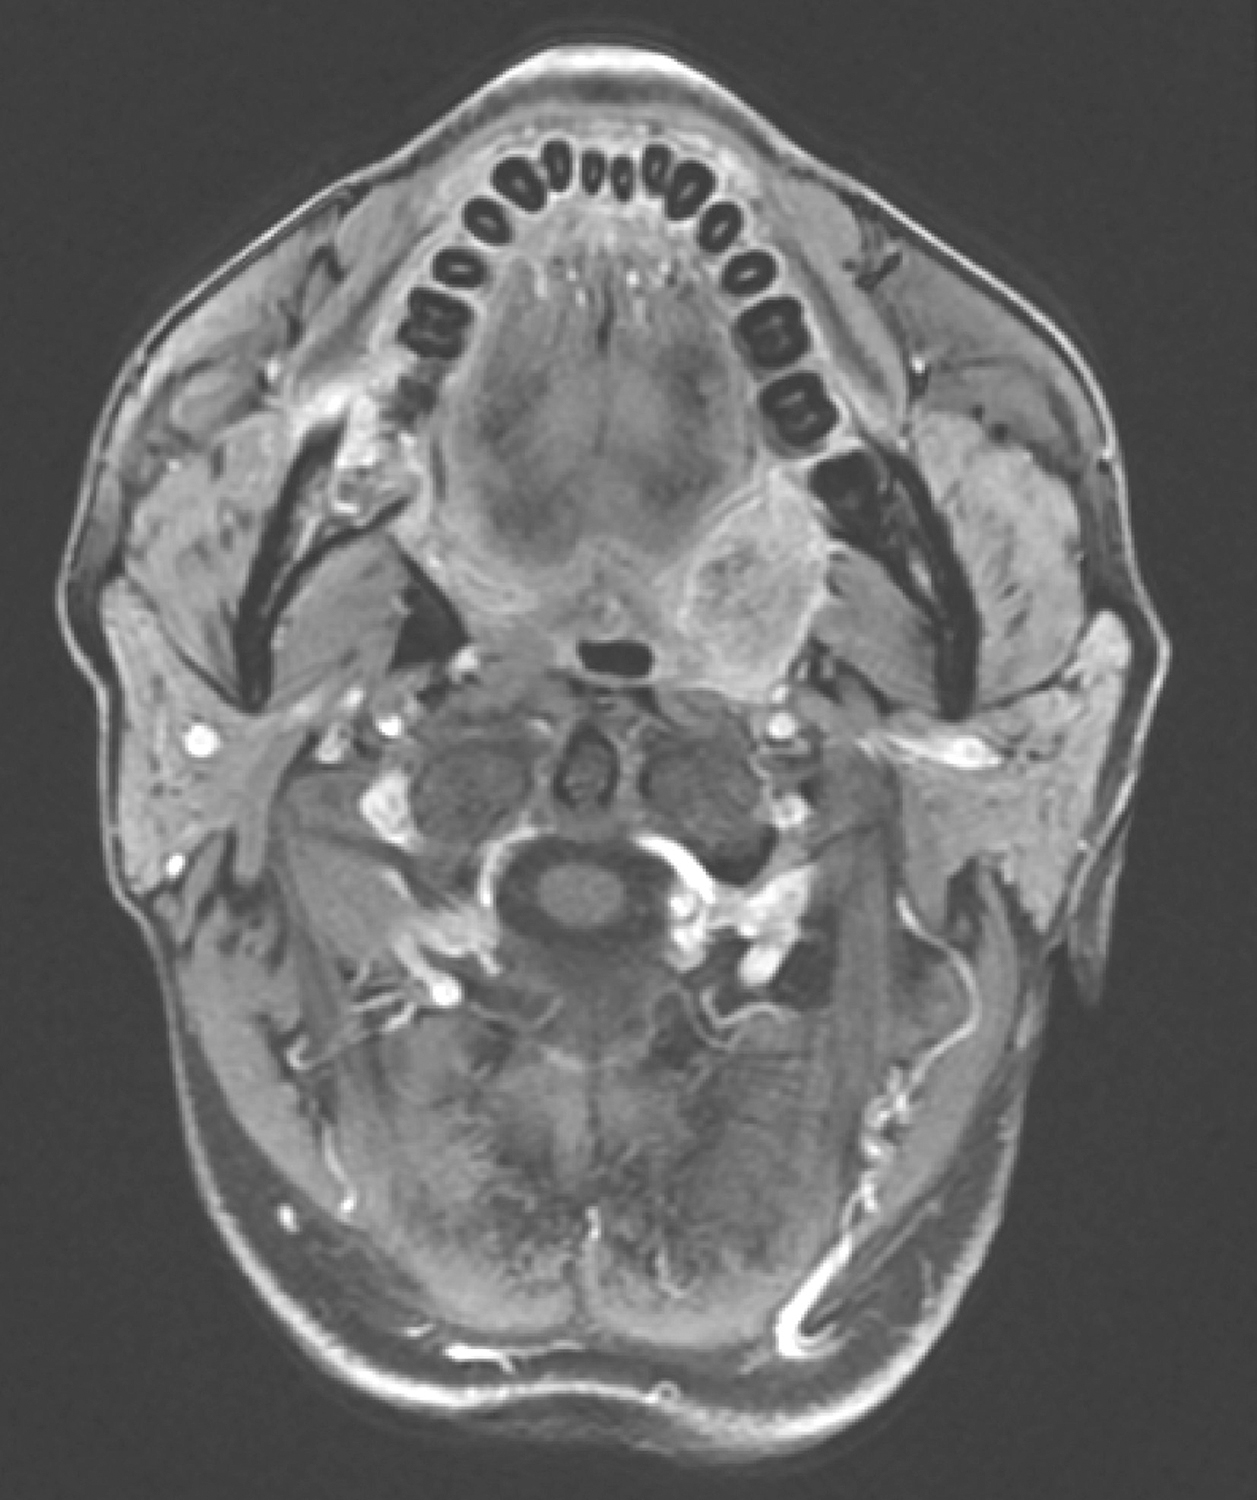

5.2016年10月19日口腔MRI

检查所见:

口咽左侧壁肿物,约2.3cm×1.8cm×2.3cm,T1WI呈等信号,T2WI/FS呈稍高信号,DWI扩散受限,增强扫描明显不均匀强化,肿物向外侵犯左侧咽旁间隙及左侧翼内肌,向下与左侧扁桃体关系密切(图4)。双侧颌下、颈深多发淋巴结,大者短径约0.8cm。

影像学诊断:

(1)口咽左侧壁肿物,考虑恶性,向外侵犯左侧咽旁间隙,贴邻左侧翼内肌,向下与左侧扁桃体关系密切。

(2)双侧颌下、颈深多发淋巴结,请随诊。

图4口腔MRI示口咽左侧壁肿物